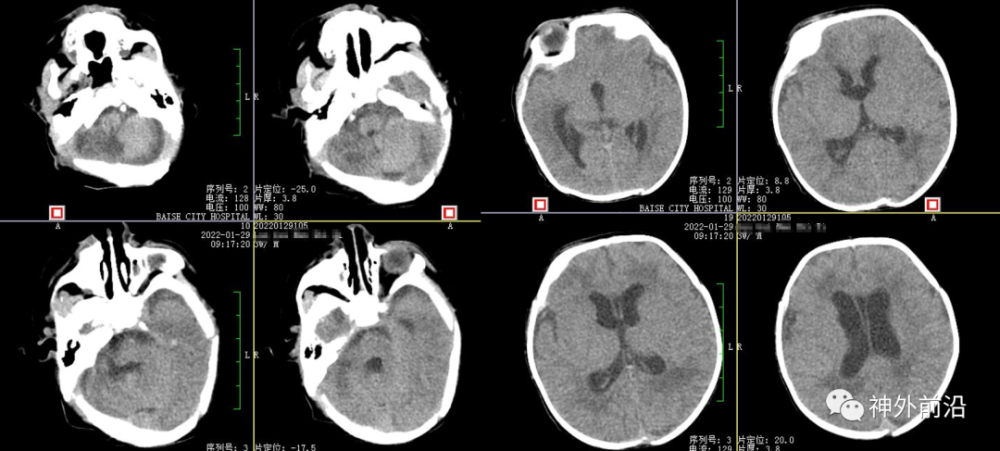

9.术后6天复查CT,血肿基本清除及夹闭侧脑室引流管

10.术后9天复查CT,拔除侧脑室引流管

11.术后17天复查CT